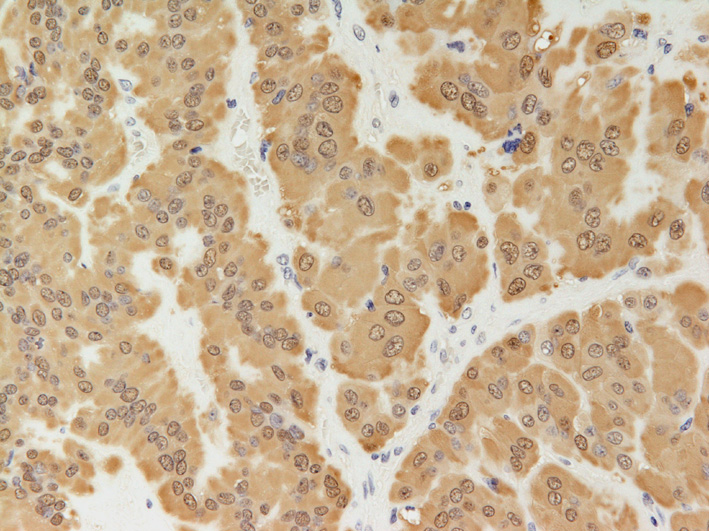

S100の免疫染色(対物x20).腫瘍細胞のほとんどに陽性像を示す. |